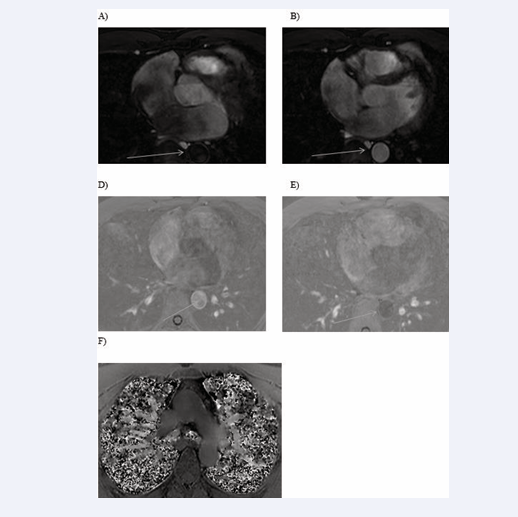

All cardiac chambers and great vessels were quantitatively analysed for CNR and SNR using Osirix software. Regions of interest (ROIs) were defined to determine the signal (S) from blood (SBlood ) in the left ventricle (LV), right ventricle (RV), pulmonary artery (PA), ascending and descending aorta (Ao), and pulmonary veins (PV) relative to the reference tissue (SMyocardium ). Noise (N) was estimated according to the standard deviation of these respective ROIs. CNR was defined by using the following equation: CNR = (SBlood -SMyocardium )/(0.5 × [NBlood +NMyocardium ]), where all variables are mean values. SNR was defined using the equation SNR = (SBlood )/(NBlood ) [9]. Image processing and reformatting were performed with commercially available analysis software (View Forum; Philips Healthcare).The image gradient system was modified based on McConnell et al [20] (Figure 2). Consensus reading was performed for image quality scoring by two readers using the image quality scores defined in Table 2. The readers analysed all images independently in a blinded and random order. Disagreements were discussed before a single final grade was given. Visual inspection was performed to identify the intracardiac and extracardiac arterial and venous structures [21] (Figures 1, 2 and 3).

Identification of intracardiac and extracardiac arterial and venous structure

Figure 1: Identification of intracardiac and extracardiac arterial and venous structure

Identification of intracardiac and extracardiac arterial and venous structures

Figure 2: Identification of intracardiac and extracardiac arterial and venous structures

Figure 3: Identification of intracardiac and extracardiac arterial and venous structures